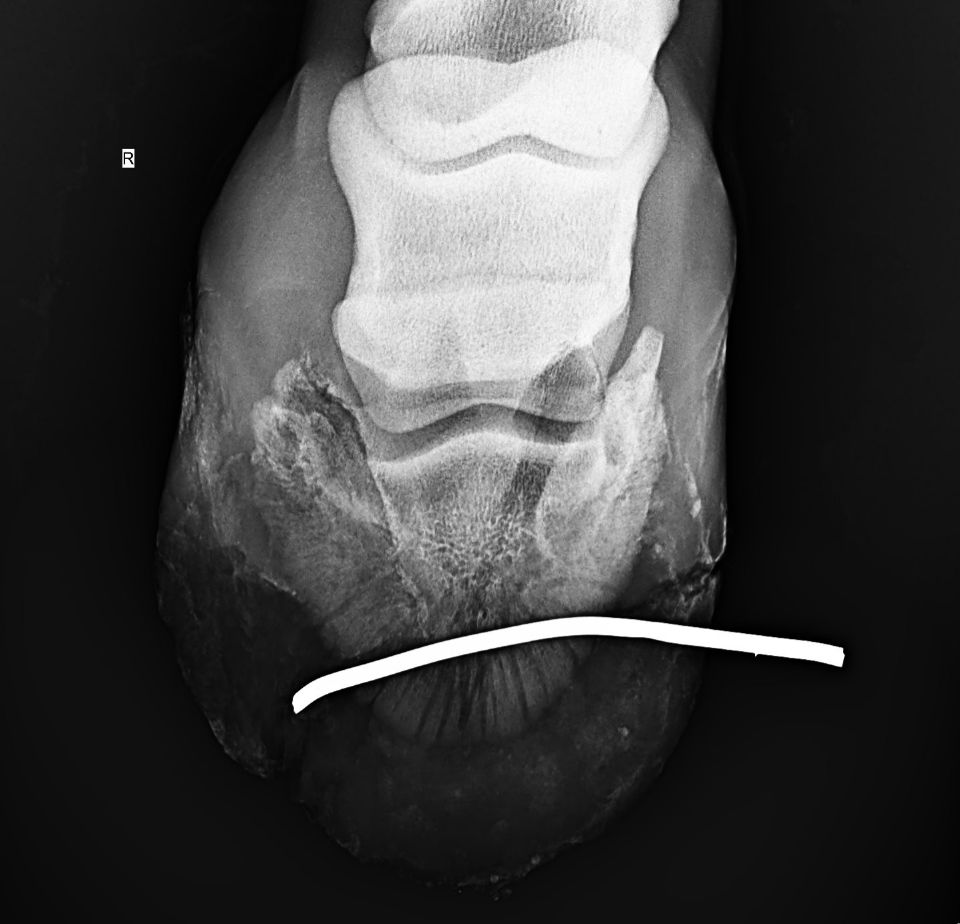

Once Peachy, who is in training to run barrels in Loxahatchee, FL, was comfortable, Dr. Demierre utilized portable radiograph technology to obtain x-ray images of the right hind foot and evaluate the injury. The images revealed that it was safe to remove the wire, and after disinfecting the area, Dr. Demierre removed the wire through the injury site.

“There were no fractures or synovial structures involved, but I did see on the radiograph that the coffin bone was compromised,” said Dr. Demierre. “There was a suspicious line through the coffin bone that could have led to chronic lameness, so the prognosis for performance was reserved. The prognosis for survival was very positive, and I told the owner there was a 50/50 chance she would return to training.”

Dr. Demierre returned to check on Peachy and continue the antibiotic treatments six times over the next two months. “I performed recheck radiographs of the hoof a month after the injury and there was no fracture where we saw the initial line that caused concern,” said Dr. Demierre. “The margins of the coffin bone had reabsorbed slightly, but overall the injury was healing well.”